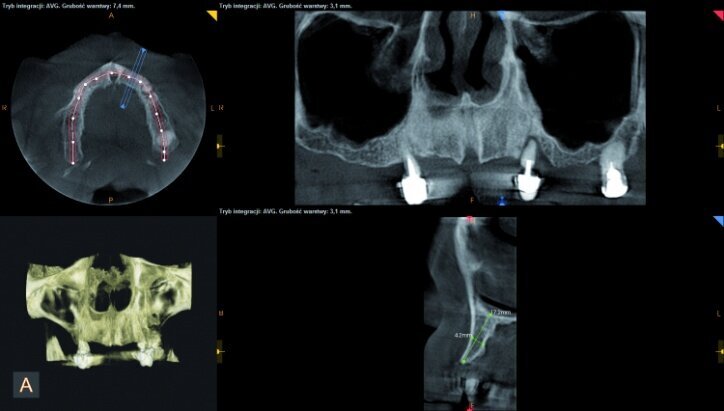

During the process of treatment planning, a few proposals for prosthetic solutions were presented, including permanent and temporary restorations, based on existing teeth as well as implants of various combinations. After analysing CBCT scans (Figs. 3–6) it could be concluded that implantological treatment may be performed at the front maxilla without any additional procedures, however, due to significant atrophy in the lateral part and a low-lying fundus of the left and right maxillary sinus, it appeared necessary to perform augmentation procedures (sinus lift), in order to make implantation possible.